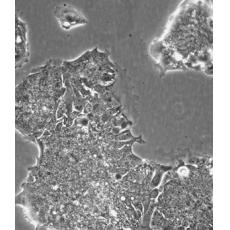

中文名稱 人結(jié)腸腺癌肺轉(zhuǎn)移細(xì)胞

組織來(lái)源 結(jié)腸腺癌;肺轉(zhuǎn)移;男性

生長(zhǎng)特性 adherent

形態(tài)特征 epithelial

細(xì)胞描述 T84細(xì)胞株是從一位72歲男性結(jié)腸癌患者的肺轉(zhuǎn)移灶建立的可移植人類癌細(xì)胞株。 腫瘤組織皮下接種于BALB/c裸鼠,并連續(xù)進(jìn)行移植。 [26072] 在裸鼠身上的移植過(guò)程中,細(xì)胞株始終保持結(jié)腸癌的原始組織性狀。 [26072] 在無(wú)胸腺小鼠中傳代23代后建立了T84細(xì)胞株。 這些細(xì)胞單層生長(zhǎng)到飽和并在接觸細(xì)胞間展現(xiàn)出緊密連接和橋粒。 [1155] 有很多關(guān)于多肽類激素和神經(jīng)遞質(zhì)并維持定向電解質(zhì)傳輸?shù)氖荏w。 [1155] 這株細(xì)胞展現(xiàn)了接觸細(xì)胞中的緊密連接和橋粒。 [1155] 角蛋白免疫過(guò)氧化物酶染色陽(yáng)性。